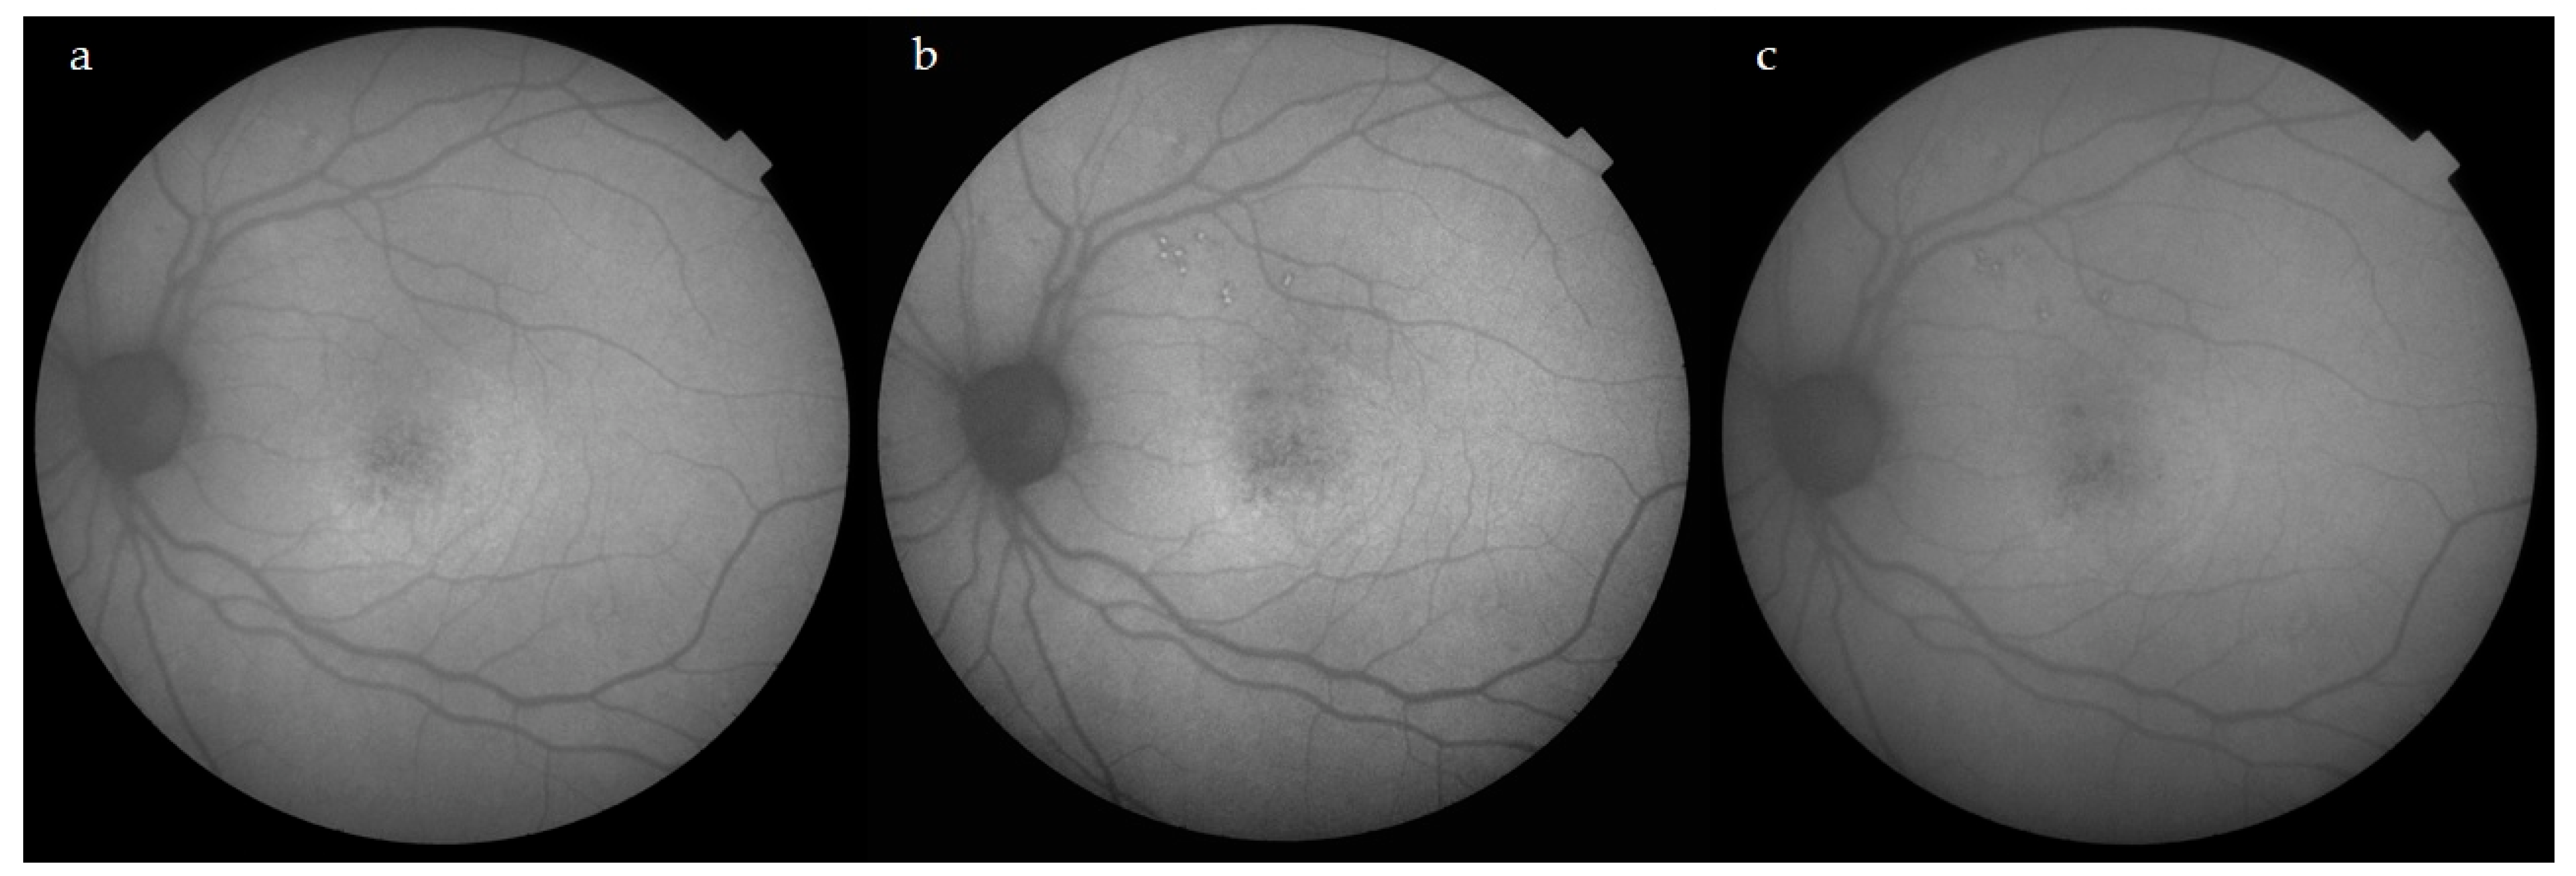

3.1. Subretinal Fluid (SRF)

3.4. Adverse Events